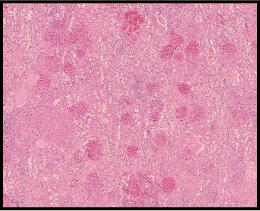

A kidney biopsy is performed to investigate the patient's declining renal function.

Histologic analysis of the kidney after death is shown to the left along with a "special stain" for fibrin.